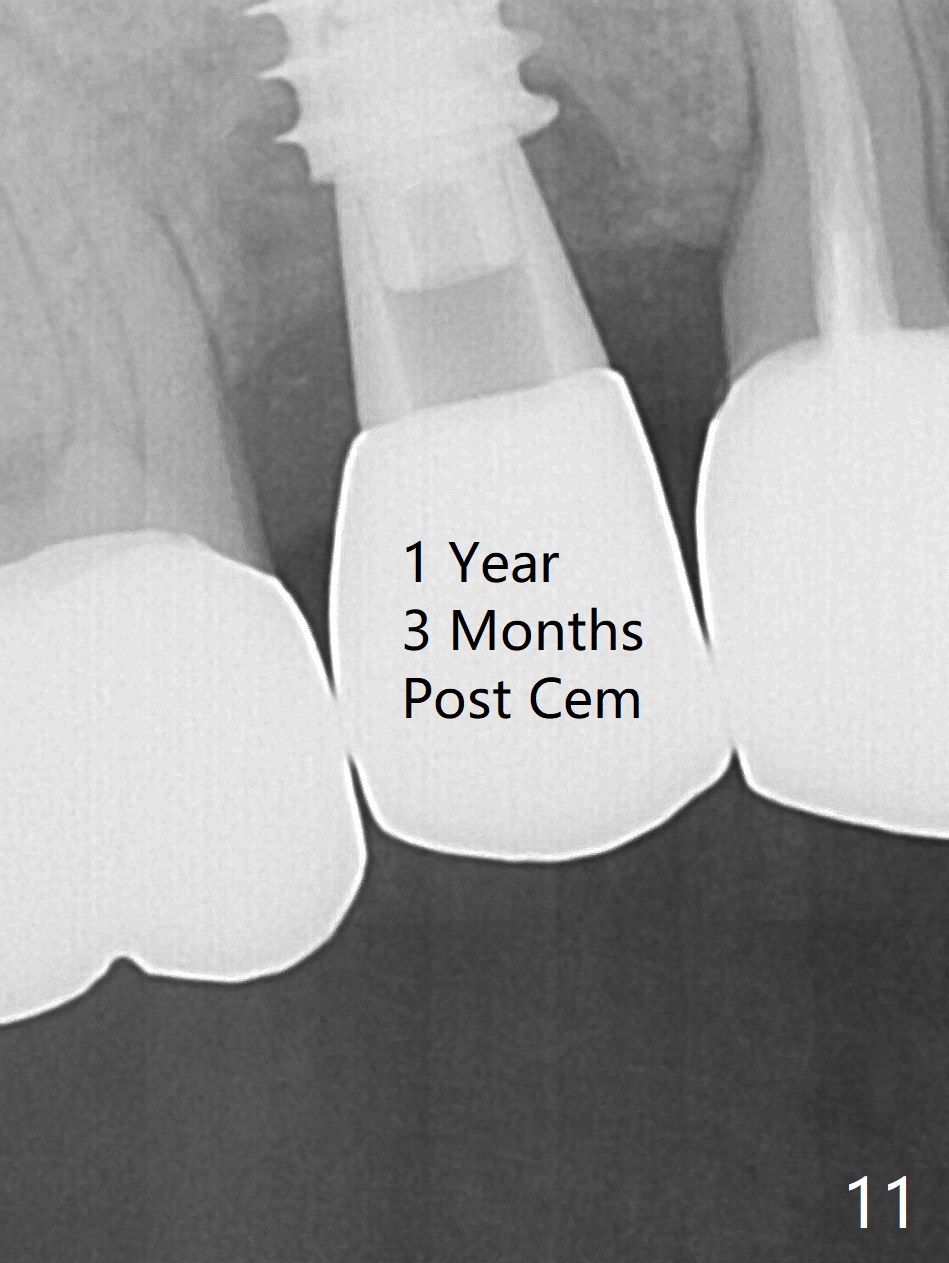

When the tooth #4 with vertical root fracture is extracted, the socket is large, approximately 6x10x10 mm (Fig.1 (mesiodistal x buccopalatal width x depth)). Osteotomy is established in the middle of the socket with 2 mm initial drill for 7 mm, 2.8 and 3.6 mm rounds drills (from DIO Sinus Master Kit) for < 7 mm, and 3.0 and 3.8 mm Magic Expanders. A 4x11 mm dummy implant is placed with insertion torque of 30 Ncm (Fig.2,3 (^: sinus floor)). There is a gap between the socket wall and the implant (*). To reduce the gap and periimplantitis, a 5x11 mm IBS implant is placed with insertion torque > 50 Ncm after further osteotomy using Magic Drills (Fig.4,5). Following placement of 5.5x4(4) mm abutment (A) and bone graft (data not shown), a splinted provisional is fabricated at #3 and 4. The provisional is stable 3 months postop (Fig.6,7). The peri-implant gaps (Fig.4,5) seem to disappear (Fig.6) with the help of bone graft. Bone graft appears to remain between the implant fins (Fig.7 arrows). Impression is taken 4.5 months postop (Fig.8,9). The abutment dislodges 4 months post cementation. After retightening, there is clearance for shim after use of 2 layers of thick articulating paper. Is the abutment screw too short? Or Titanium V is too hard for welding? The abutment/crown dislodges again 1 year 3 month post cementation; it appears that the fact that the implant is placed deep contributes to abutment screw loosening (Fig.10,11). An abutment screw will be buried inside the implant well 10 days post initial retightening.